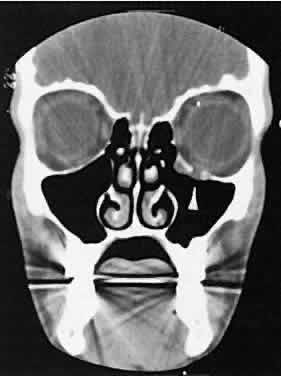

The edema and inflammatory infiltrate that accompany infections are indistinguishable from that associated with orbital inflammations. The presence of sinus disease, however, is a more constant feature with infections, because the sinus represents the infectious nidus in most cases (Fig. 9). In addition to the frequent appearance of sinus disease, the adjacent EOM is invariably enlarged. Less often, orbital infections may be transmitted through the blood, related to a retained foreign body, or spread from the lids. Chandler and colleagues47 classified orbital infections into five groups. Group 1 (preseptal cellulitis) represents inflammatory edema and reflects congestion of venous outflow. Group 2 has actual orbital infiltration/edema with mass effects and functional deficits. Group 3 includes patients with subperiosteal abscesses. Most of these dome-shaped subperiosteal abscesses are located along the medial wall. Group 4 includes patients with orbital abscesses who may display a ring-enhancing lesion with mass effect. Group 5 represents intracranial extension of the inflammation into the cavernous sinus or sinuses, which appear engorged and opacified.

Fig. 9. Orbital cellulitis. A. Axial view shows a subperiosteal soft-tissue mass displacing the medial rectus muscle. The ethmoidal sinus is opacified secondary to inflammatory disease, which invariably precedes the orbital inflammation. B. Coronal view further shows the subperiosteal and ethmoidal sinus inflammation. Inflammation changes also are seen in each maxillary sinus.